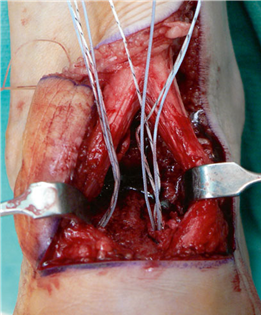

The Lapidus Arthrodesis (First TMT Fusion)

For severe deformities or hypermobility, the Lapidus procedure provides robust stabilization of the medial column. A dorsal or medial incision is utilized over the first TMT joint. The extensor hallucis longus (EHL) is retracted dorsally, and the tibialis anterior tendon is identified and protected at its insertion on the medial cuneiform and first metatarsal base. The TMT joint capsule is incised, and the joint is thoroughly debrided of all articular cartilage using a combination of osteotomes, curettes, and a high-speed burr.

To achieve multiplanar correction, the surgeon must address the sagittal, coronal, and transverse planes. The first metatarsal is plantarflexed to restore the longitudinal arch, rotated out of pronation to realign the sesamoids, and translated laterally to close the IMA. Subchondral drilling or feathering is performed to optimize the biological environment for fusion. Fixation is traditionally achieved with two or three crossed solid or cannulated screws (typically 3.5mm or 4.0mm). Recently, plantar or medial locking plates have gained immense popularity due to their superior biomechanical construct, allowing for earlier weight-bearing. Bone graft or orthobiologics may be packed into the arthrodesis site to stimulate osteogenesis.